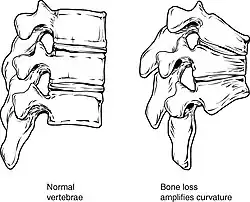

Iliocostal friction syndrome most commonly occurs bilaterally as a result of spinal osteoporosis.[2] Osteoporosis is a condition in which the bone density and quality deteriorates, resulting in an increased risk for fractures. More than 2 million fractures occur annually in the United States due to osteoporosis.[9] The most common fractures that occur due to osteoporosis is in the hip or vertebrae,[10] resulting in a loss of space between the ribs and the iliac crest. It is estimated that osteoporosis can cause 25% of females over 50 years of age within the United States to have at least one vertebral fracture in their lifetime.[11] Factors that make an individual more at risk for experiencing a fracture includes age, sex, weight, height, family history, rheumatoid arthritis, previous fracture, secondary osteoporosis, alcohol or smoking use, glucocorticoid use, and the femoral neck bone mineral density of the individual.[10]

Another cause for bilateral iliocostal contact is based on the kyphosis curve of the spine. The thoracic spine is slightly curved due to the shape of the vertebral bodies and intervertebral discs, with a normal Cobb angle measurement between 20 and 40 degrees. Hyperkyphosis is a condition in which the curve of the kyphosis angle measures over 50 degrees. The kyphosis angle can be influenced by age, muscle tone,[12] vertebral fractures, and intervertebral degenerative disc disease.[13] Hyperkyphosis can result from posture, a congenital deformity, heritable conditions such as Scheuermann's disease,[14] tumours, trauma, neuro-muscular disease, postlaminectomy syndrome, dwarfism, and infections such as tuberculosis which can result in Pott's disease.[15] The curvature of hyperkyphosis may result in a decrease of space between the ribs and the iliac crest, causing iliocostal friction syndrome.[11]